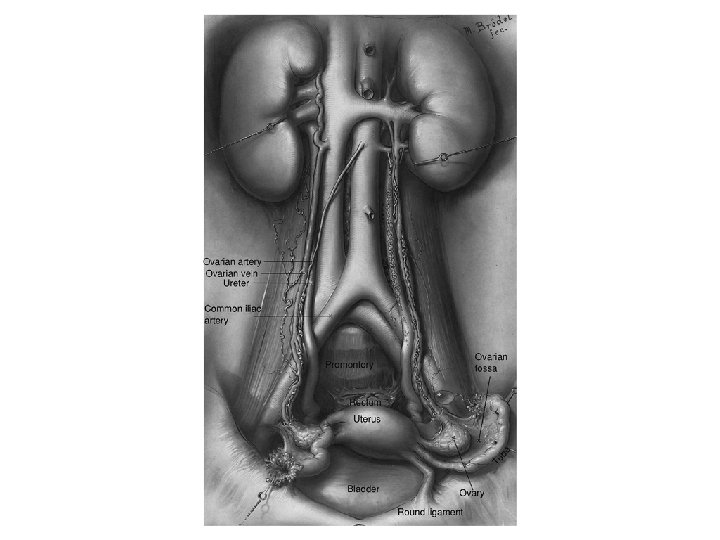

Pelvic Vasculature Sakralis Media İnternal iliak (hipogastrik) Common Iliac İliolumbar Lateral Sakral Superior Gluteal Inferior Gluteal Orta Hemoroidal Pudendal Uterin Inferior Vesika Umbilical Obturator Burnett Novack’s Gynecology 20

Branches of the Internal Iliac Artery Anterior Division Posterior Division Uterine Umbilical Uterine vesical Obturator Internal pudendal Inferior gluteal Middle vesical Middle rectal Vaginal Superior gluteal Lateral sacral Iliolumbar

Collateral Arterial Circulation of the Pelvis Primary Artery Aorta Ovarian artery Superior rectal artery (inferior mesenteric artery) Lumbar arteries Vertebral arteries Collateral Arteries Middle sacral artery Lateral sacral artery External Iliac Deep iliac circumflex artery Inferior epigastric artery Iliolumbar artery Superior gluteal artery Obturator artery Femoral Medial femoral circumflex artery Lateral femoral circumflex artery Obturator artery Inferior gluteal artery Superior gluteal artery Iliolumbar artery Uterine artery Middle rectal artery Inferior rectal artery (internal pudendal) Iliolumbar artery

• Ovarian arteries – Originate directly from the aorta, inferior to the renal arteries. – Most frequently identified at the IP ligament. • Ovarian veins: – Left ovarian vein drains into the left renal vein – Right ovarian vein drains directly into the inferior vena cava.